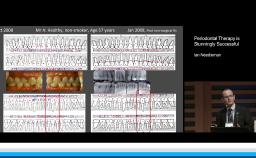

This presentation introduces and addresses the physiologic changes that occur in the oral cavity with age. Particular focus is given to the dental and periodontal tissues, oral mucosa, salivary glands, and the alveolar process (or alveolar bone). A differentiation is made between changes associated with age and those associated with pathology or therapy, particularly in regard to bone. General considerations are provided regarding treatment planning of elderly patients for dental implants.

- describe the general physiologic changes that occur in the oral cavity with age

- differentiate between physiologic changes and pathologic or therapy-induced changes